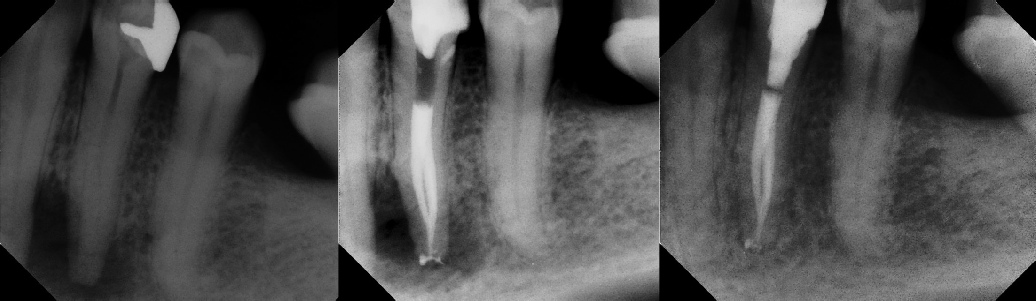

Pre-op Post-op 6 mos.